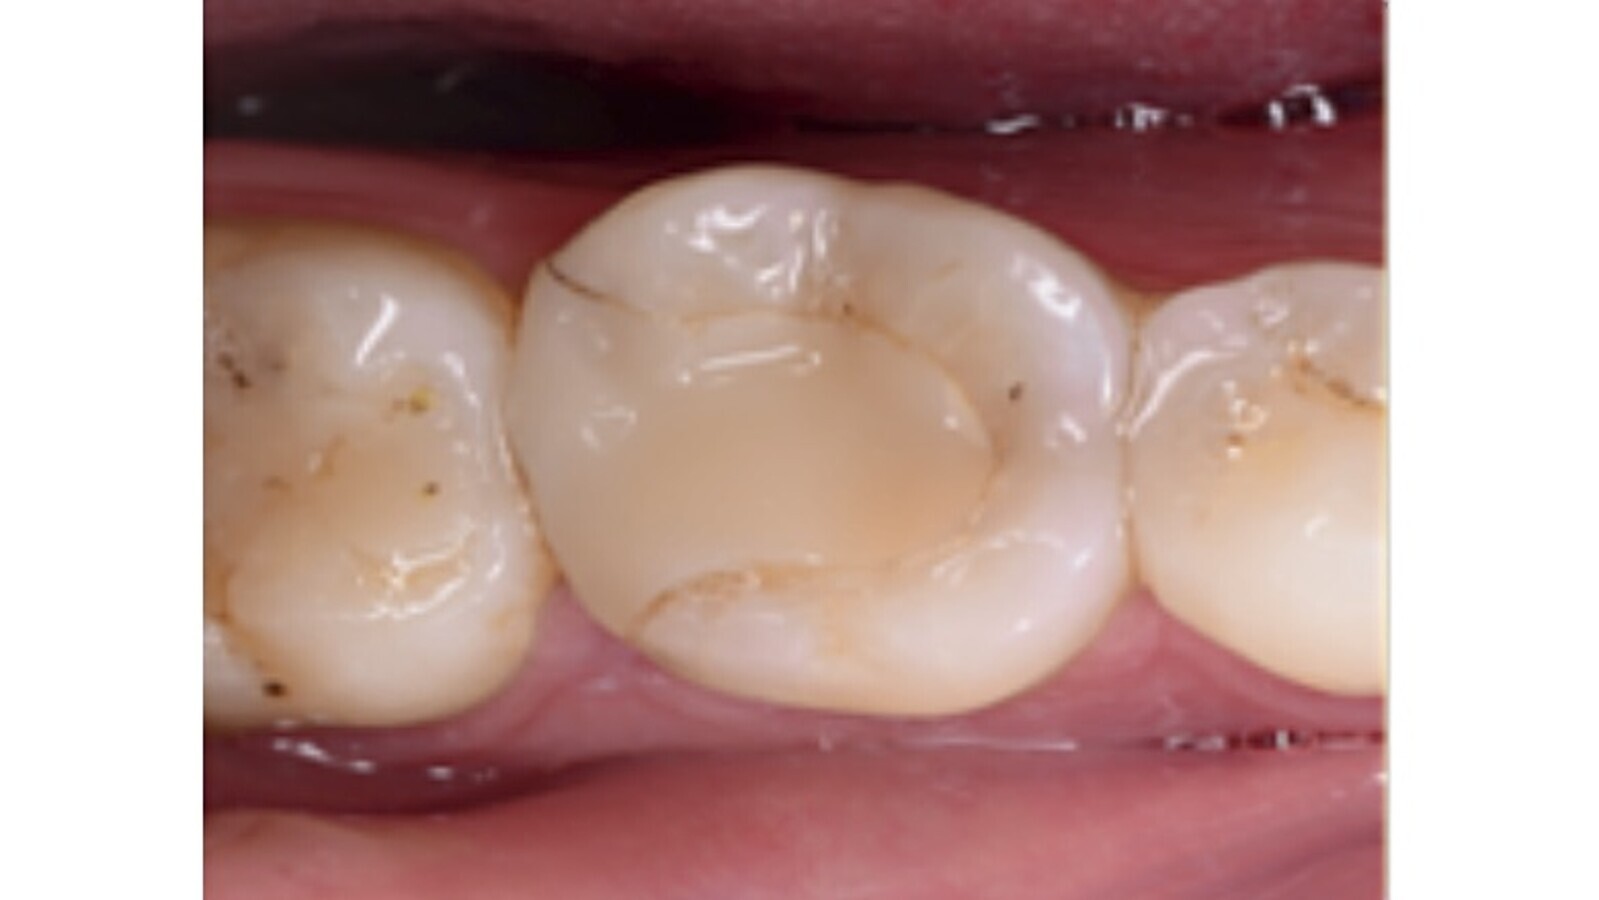

Fig. 3. Imagen clínica inicial del diente 3.6.